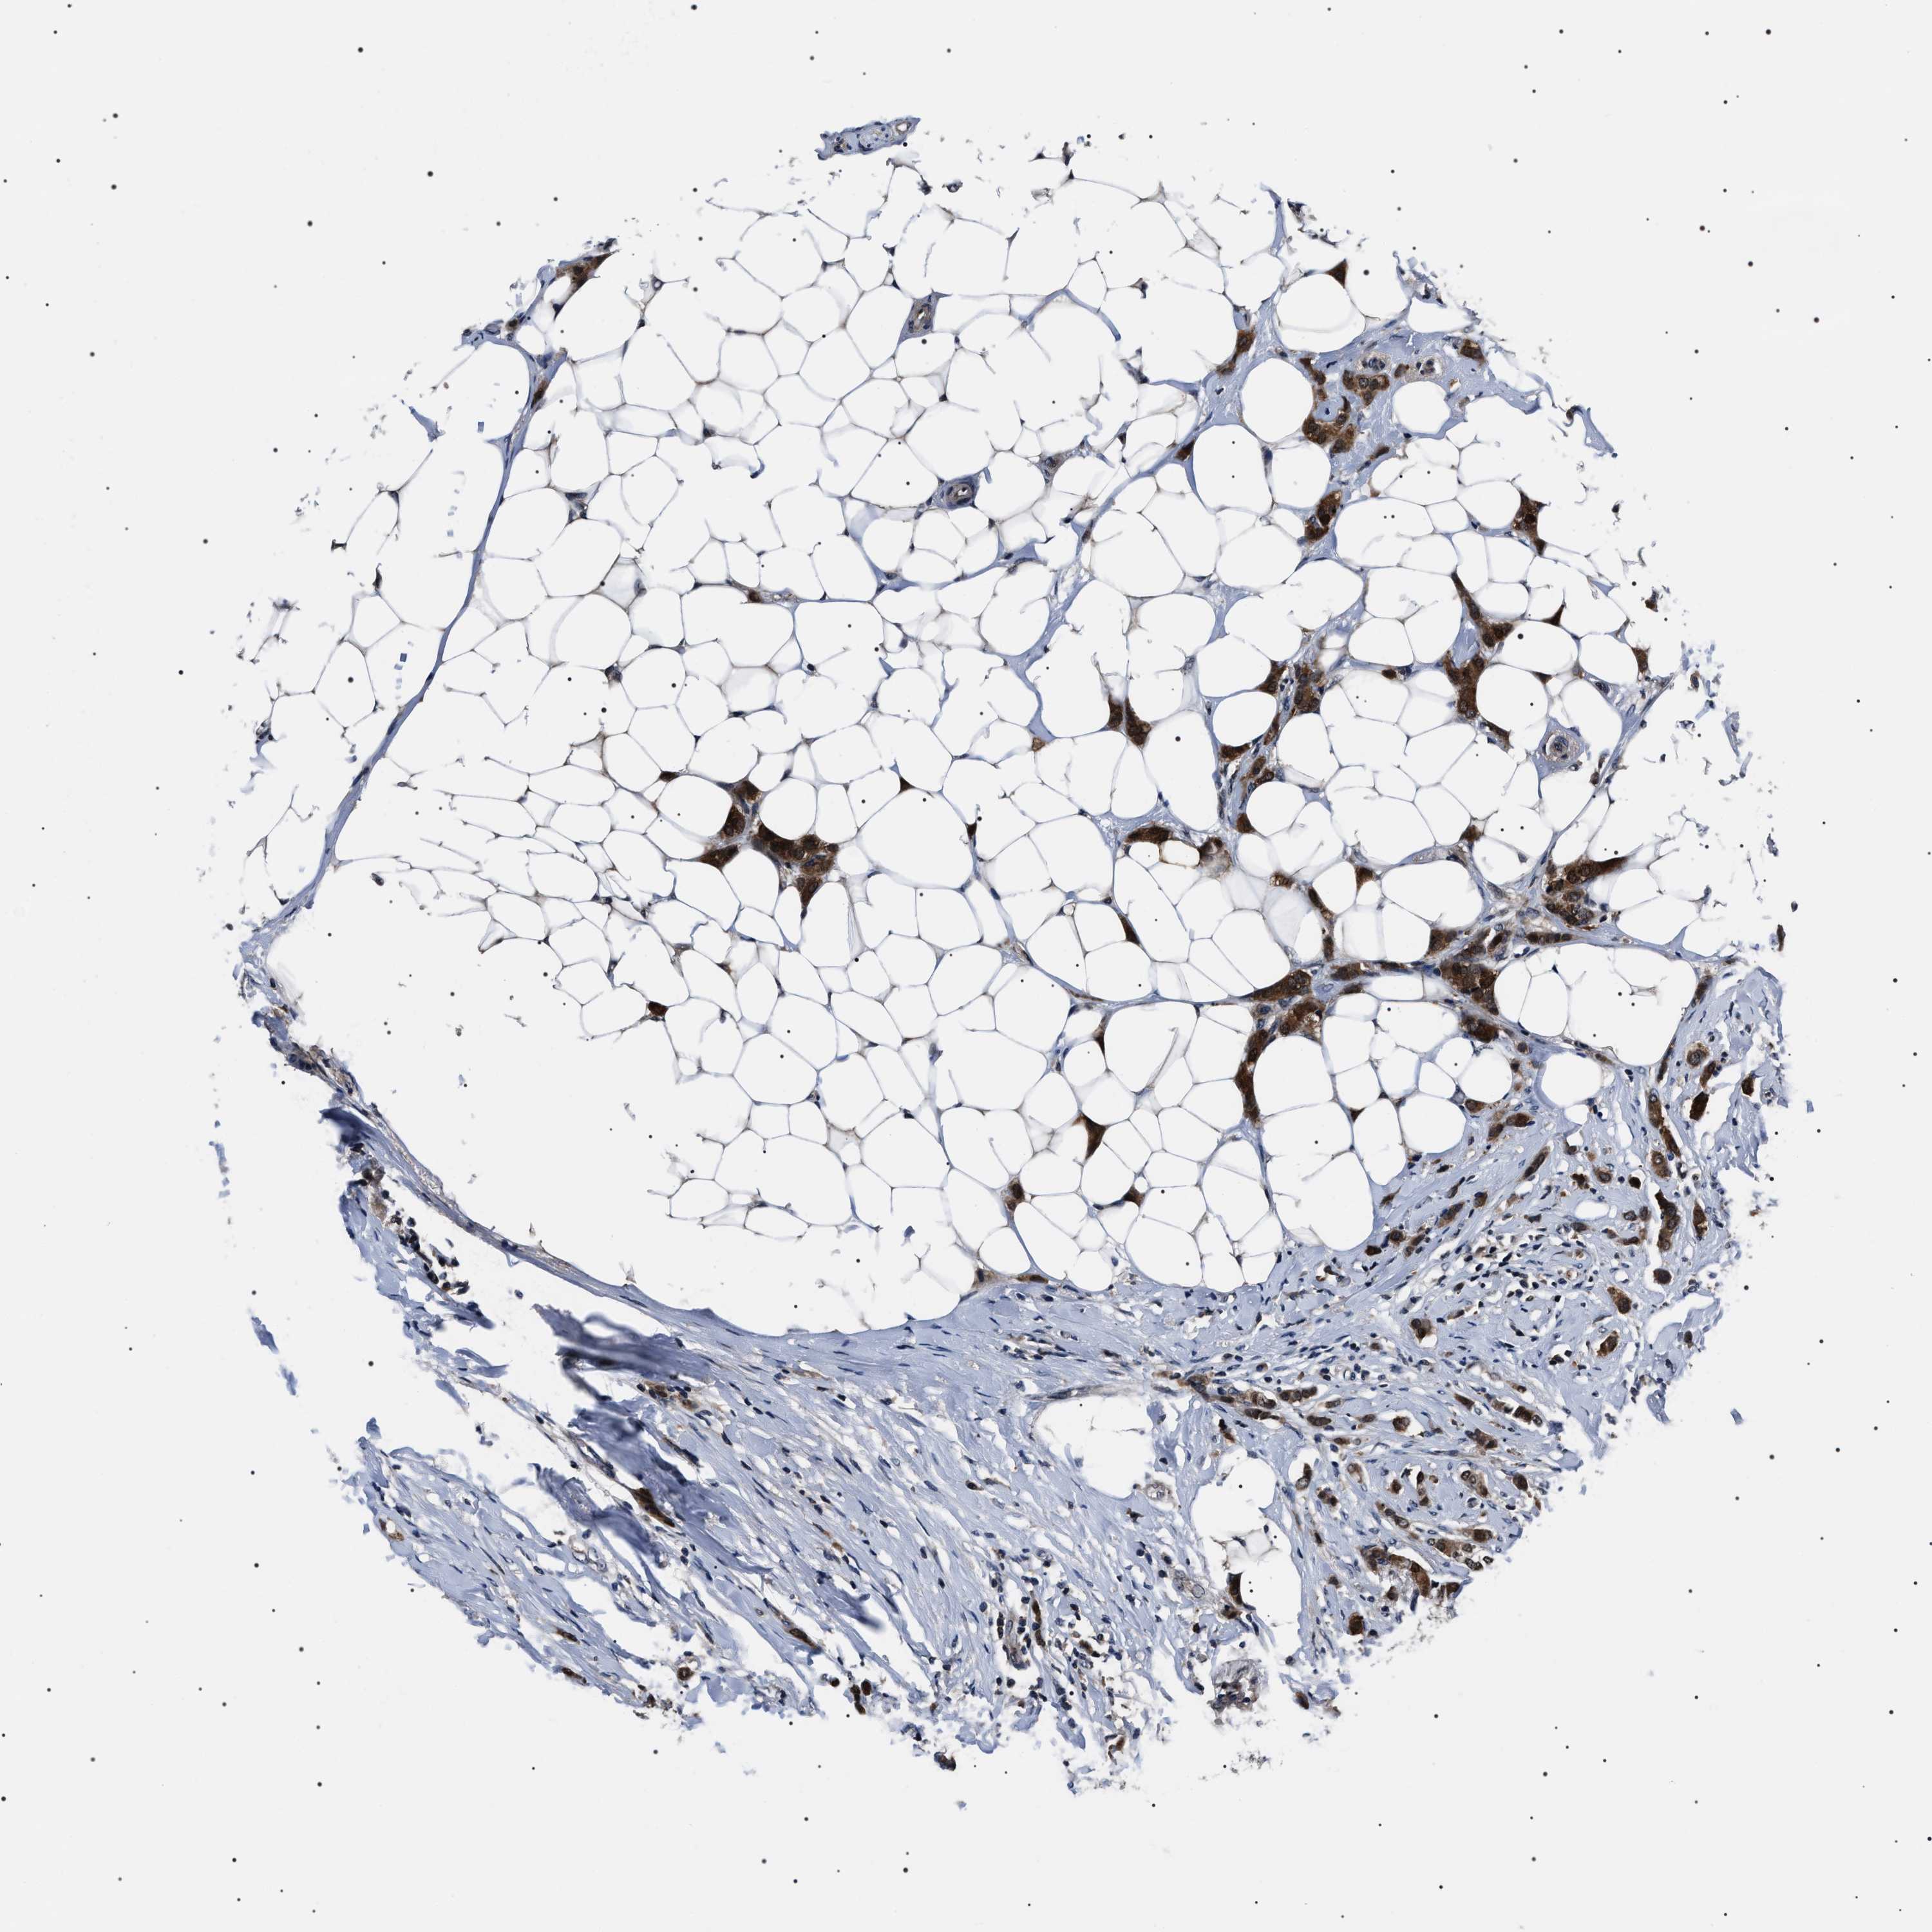

CANCER BREAST CANCER Show tissue menu

BRCA TCGA BRCA VALIDATION PROTEIN EXPRESSION